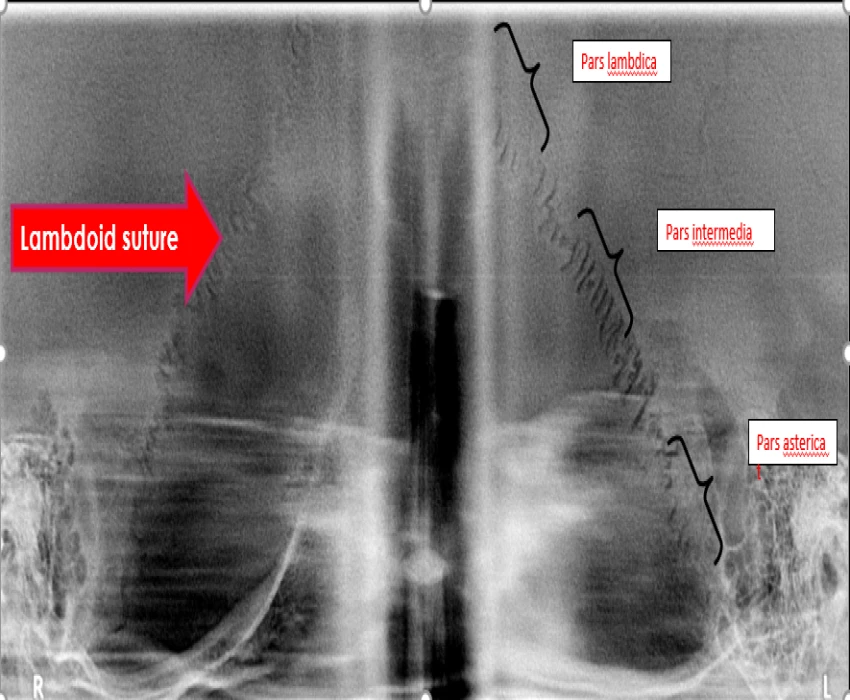

Reverse panoramic Radiography is a useful and promising technique for the initial preliminary imaging of the various anatomic structures like temporomandibular joint and its associated structures, mastoid air cell, lambdoid suture and occipital region and can be further explored in the near future.